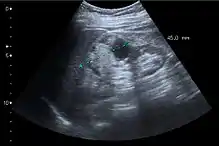

Renal cell carcinoma with both cystic and solid components located in the cortex. Measurement of tumor on the US image is illustrated by ‘+’ and a dashed line.[3]

On renal ultrasonography, a solid renal mass appears in the US exam with internal echoes, without the well-defined, smooth walls seen in cysts, often with Doppler signal, and is frequently malignant or has a high malignant potential. The most common malignant renal parenchymal tumor is renal cell carcinoma (RCC), which accounts for 86% of the malignancies in the kidney. RCCs are typically isoechoic and peripherally located in the parenchyma, but can be both hypo- and hyper-echoic and are found centrally in medulla or sinus. The lesions can be multifocal and have cystic elements due to necrosis, calcifications and be multifocal (Figure 8 and Figure 9). RCC is associated with von Hippel–Lindau disease, and with tuberous sclerosis, and US has been recommended as a tool for assessment and follow-up of renal masses in these patients.[3]